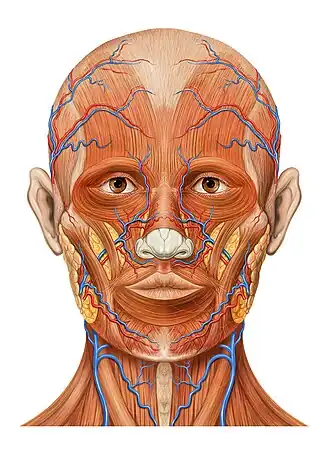

Head anatomy anterior view

Head anatomy anterior view